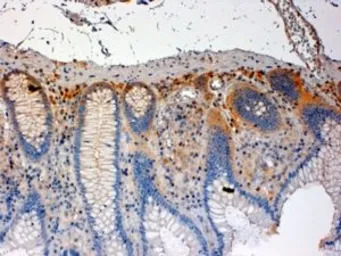

IHC-P analysis of human colon using GTX89784 CSK antibody, C-term.

Antigen retrieval : citrate buffer pH 6

Dilution : 4μg/ml